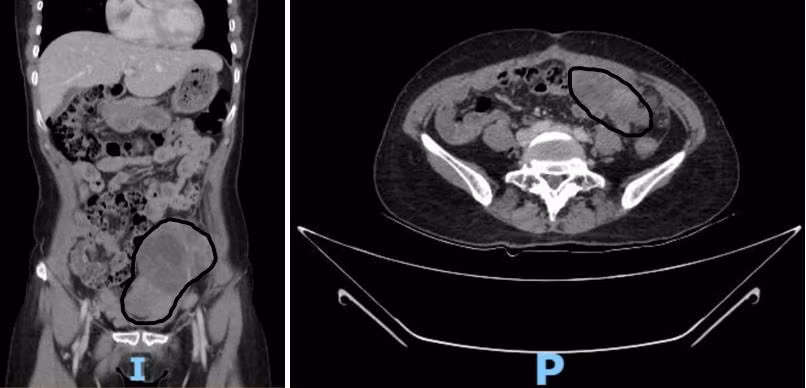

Đến năm 2024, bệnh nhân nhận thấy bụng to dần nên nhập viện tại Bệnh viện Ung Bướu TP Cần Thơ. Kết quả CT scan ghi nhận, khối tổn thương đậm độ mô mềm kích thước khoảng 150 x 102 mm và 81 x 52 mm, kèm dịch ổ bụng và thâm nhiễm mỡ mạc treo, gợi ý nhiều đến u ác tính buồng trứng di căn ổ bụng.

Hình 1. Hình ảnh khối u trên CTscan bụng theo các mặt cắt đứng dọc và ngang ghi nhận khối u ổ bụng rất to, giới hạn không rõ với các cơ quan khác - Ảnh BVCC